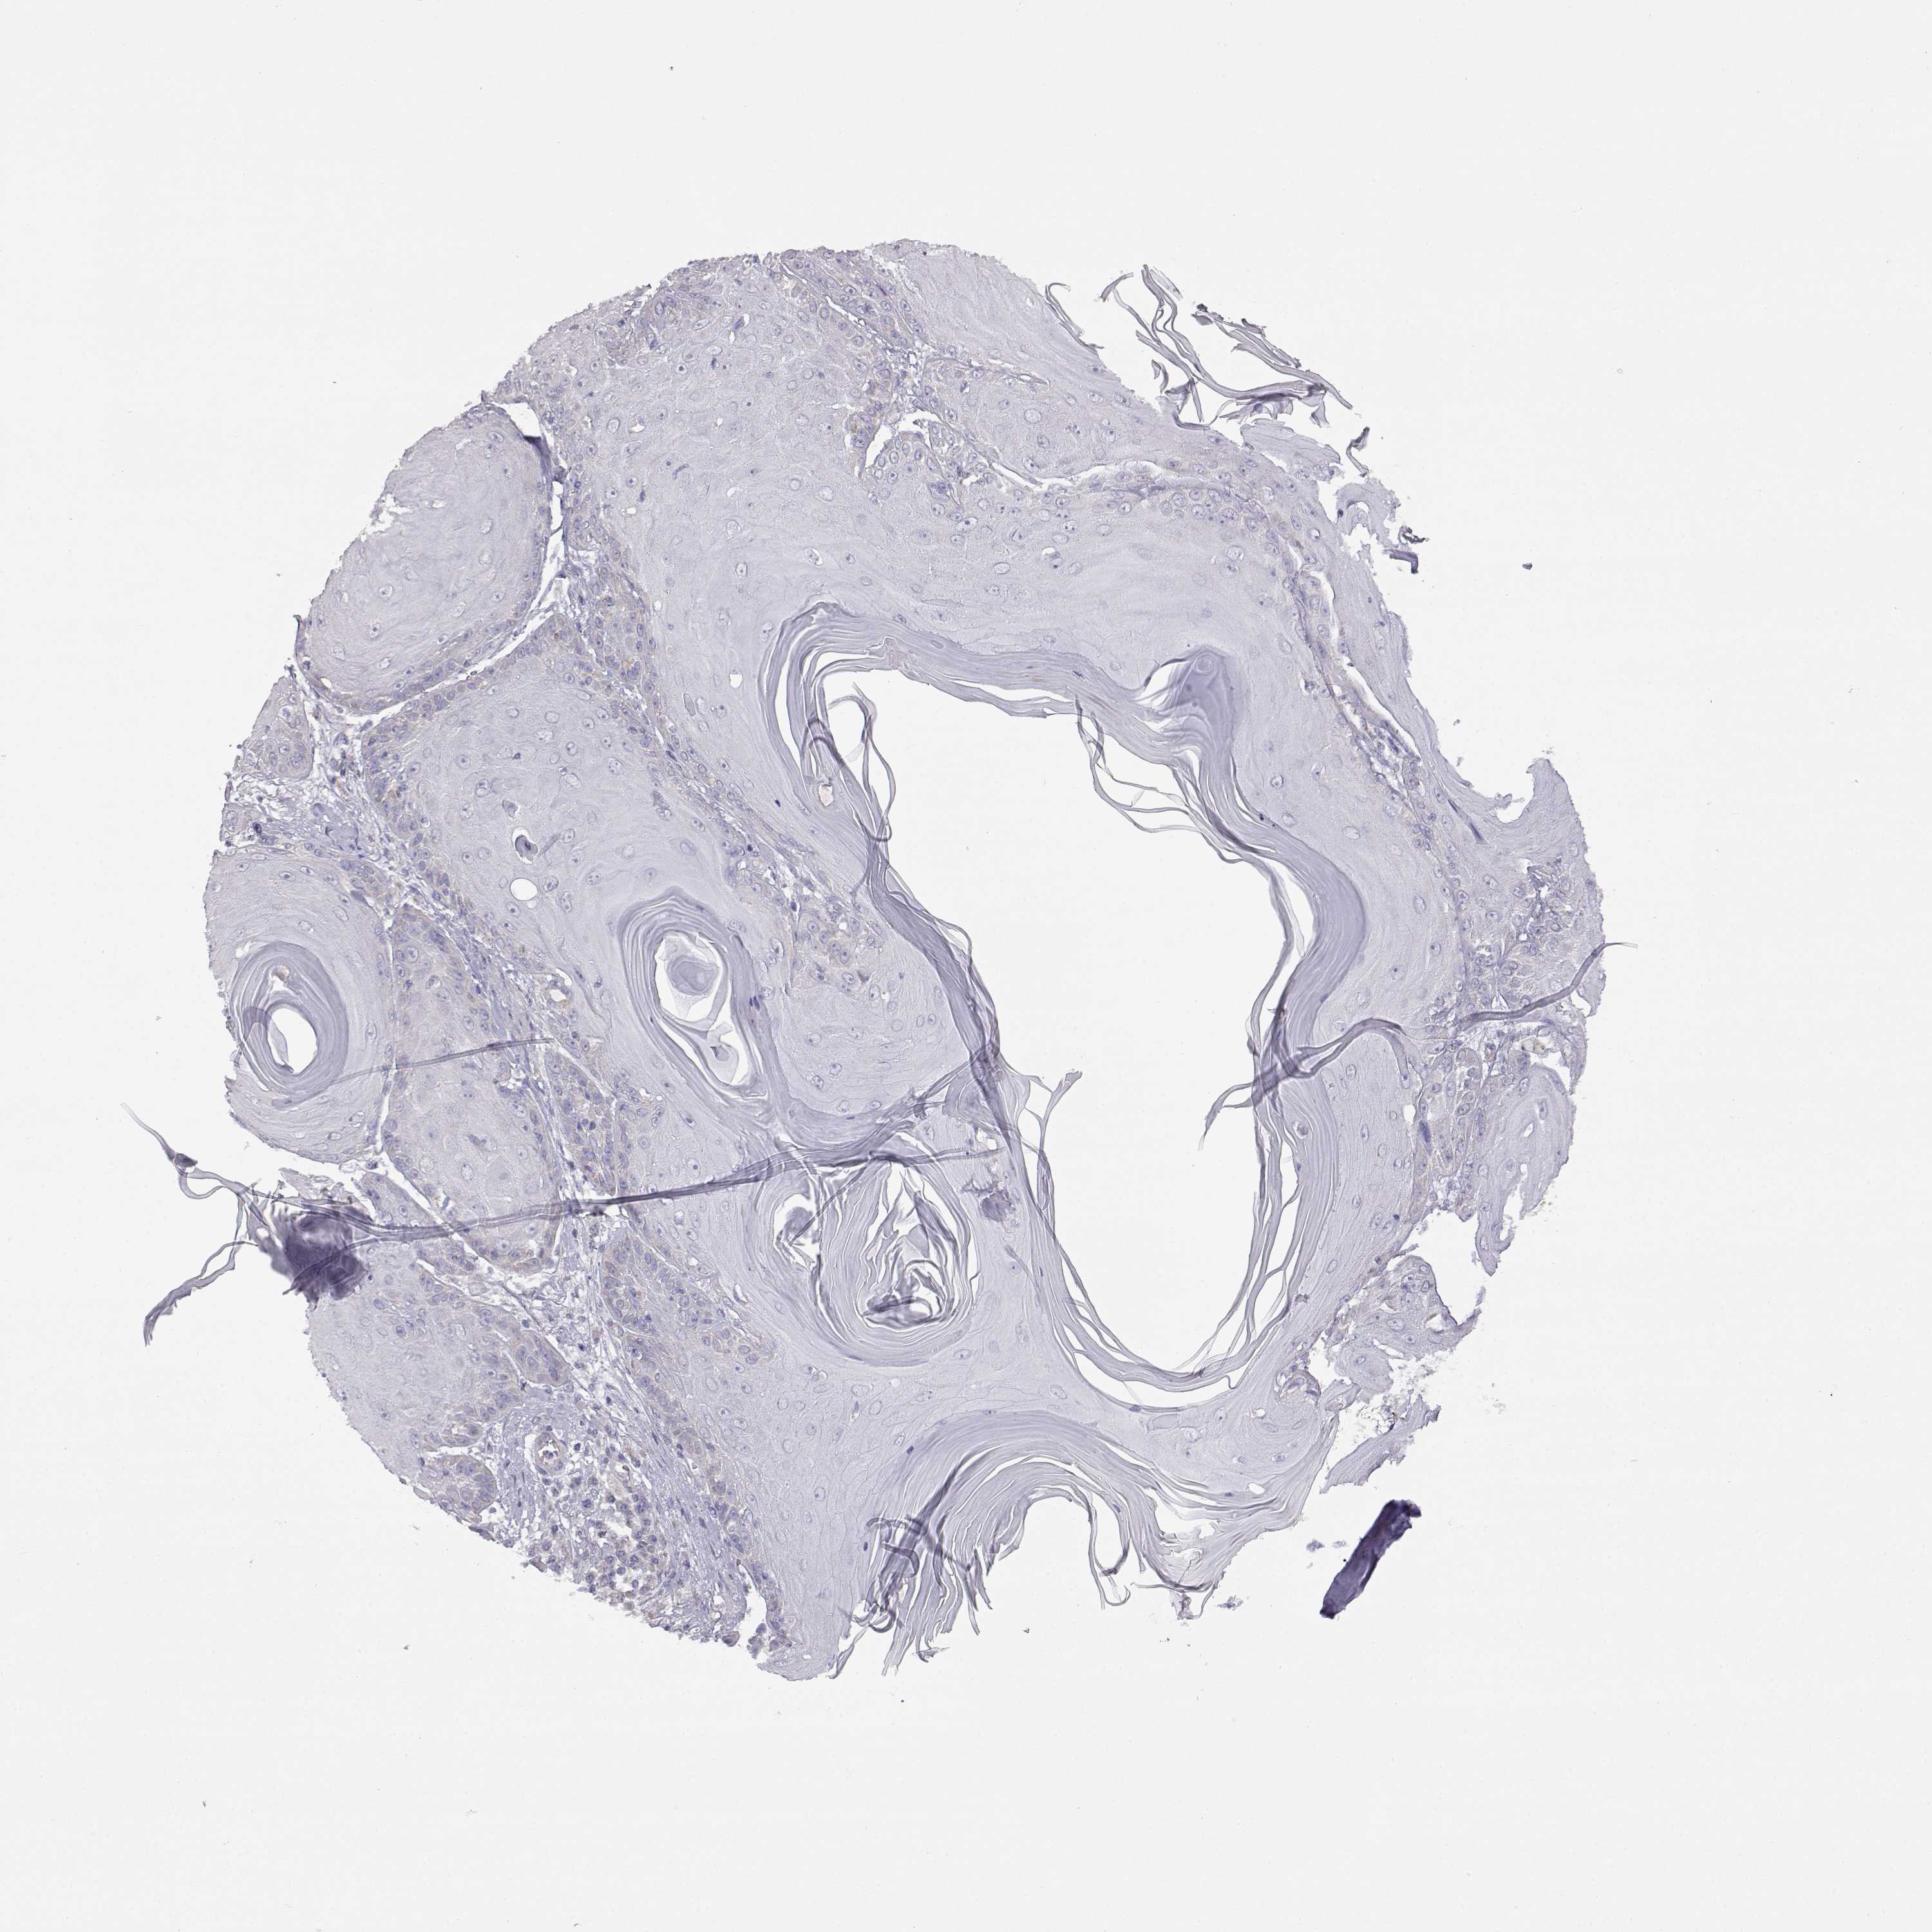

Basal cell and squamous cell cancer

SKIN CANCER - Protein expressioni

A mouse-over function shows sample information and annotation data. Click on an image to view it in a full screen mode. Samples can be filtered based on level of antibody staining by selecting one or several of the following categories: high, medium, low and not detected. The assay and annotation is described here.

Each image is clickable and will lead to virtual microscopy that enables deeper exploration of all samples and also displays staining intensity scores, fraction scores and subcellular localization as well as patient and tissue information for each sample.

Antibody HPA017742

Basal cell carcinoma

Squamous cell carcinoma, NOS